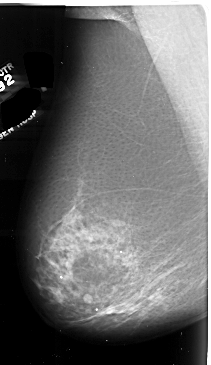

A_1008_1.RIGHT_MLO

RIGHT_MLO LINES 6526 PIXELS_PER_LINE 3826 BITS_PER_PIXEL 16 RESOLUTION 42 OVERLAY